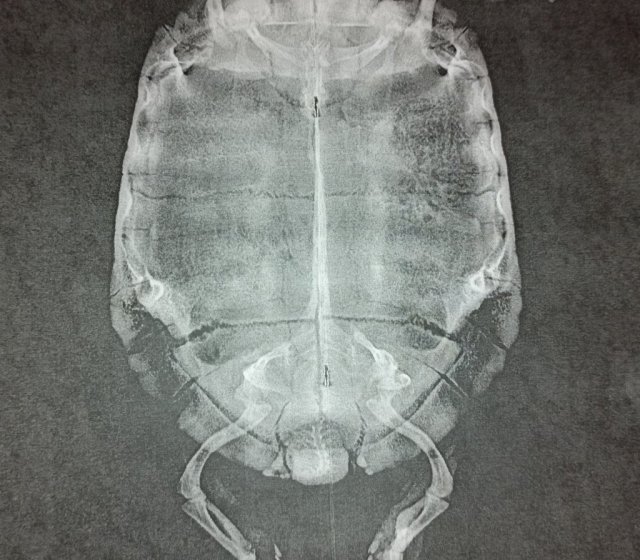

В итоге ставки были на перелом. Вчера не приеме у герпетолога сделали рентген, на котором перелома лапки не было обнаружено. И врач сказал что это невралгия и это может остаться на всю жизнь, а может пройти. То есть просто ждать и надеяться, что лапа перестанет болеть.

Потом на снимке она заметила проблему в тазобедренном суставе. Получается как раз со стороны больной лапки. Это или перелом или вывих, ничего конкретного я от нее не услышала.Никаких рекомендаций герпетолог не дала, просто сказала обеспечить черепахе покой. Ещё в случае если проблема не исчезнет рекомендовала сделать КТ, но сказала у нас в городе его не делают. Но дала номер специалиста, у которого можно узнать по этому поводу. Сказала наблюдать 3 недели за черепахой и в случае чего узнать по поводу КТ у него.

В заключении диагноз не написали, в предварительном диагнозе: травма таза.